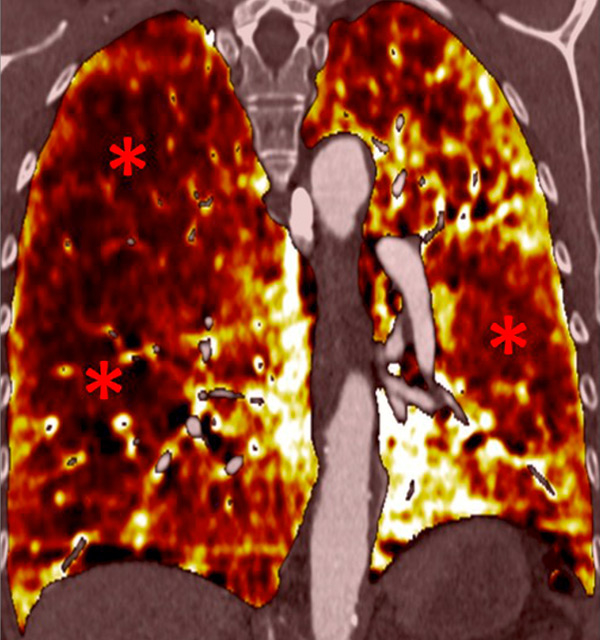

Figure 6

Perfusion heterogeneities in idiopathic pulmonary artery hypertension (stars) in two different patients (A/B). The dilatation of the arteries in pulmonary hypertension (arrows) is not always observed depending on the severity of pulmonary hypertension.

Nowadays, DECT imaging can be used for pathologies other than CTEPH and seems to offer advantages for PH characterisation because different DECT findings have been described in acute pulmonary embolism, CTEPH and idiopathic PAH (IPAH). In fact, perfusion defects are smaller and less defined in PAH than in CTEPH. This is likely due to focal under- and overperfusion as a result of the structural pulmonary vascular changes that occur in PH, which include vascular endothelial damage, cellular proliferation and occlusion in the distal pulmonary vasculature. Perfusion heterogeneities in DECT imaging are also common and seen in most cases of PAH. Findings of perfusion inhomogeneities related PAH have long been recognised in scintigraphy, and often are referred to as having a “mottled” pattern [42]. These perfusion defects are different from those seen in CTEPH, with nonsegmental and poorly defined defects (fig. 5). This heterogeneity is related to the severity of the disease. In PAH, this perfusion variability on scintigraphy is well correlated with pulmonary vascular resistance, as Talwar et al. showed [43]. Recently, similar results were published for DECT techniques (fig. 6). Ameli-Renani et al. described an increased enhancement of pulmonary arteries with reduced iodine lung perfusion in PH, and a good correlation of DECT perfusion heterogeneities with pulmonary vascular resistance; they showed a greater heterogeneity in parenchymal iodine maps in PH without pulmonary embolism [13]. The authors concluded that perfusion heterogeneities seen in DECT appear to be a direct reflection of pulmonary vascular resistance.